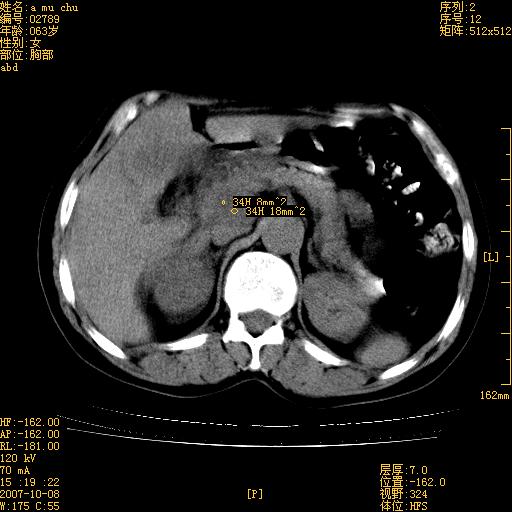

以下是引用王维浦在2007-10-17 21:02:00的发言:[br]胆囊增大,囊壁明显不规则增厚,邻近肝组织浸润,肝内外胆管无扩张。诊断:胆囊ca;[br]胰头软组织肿块影,考虑是由转移肿大的胰后淋巴结、没有肠道准备的十二指肠及胰头共同形成。[br]

以下是引用zhangzexing在2007-10-18 7:13:00的发言:[br]支持胰头占位,慢性胆囊炎. 2.肝左叶前外侧段占位,血管瘤?建议增强

以下是引用影像实习生在2007-10-17 19:49:00的发言:[br]支持胰头占位,慢性胆囊炎. 2.肝左叶前外侧段占位,血管瘤?建议增强.

以下是引用刘振江在2007-10-17 19:42:00的发言:[br]没有增强,胰头癌?胆囊及肝左叶占位?